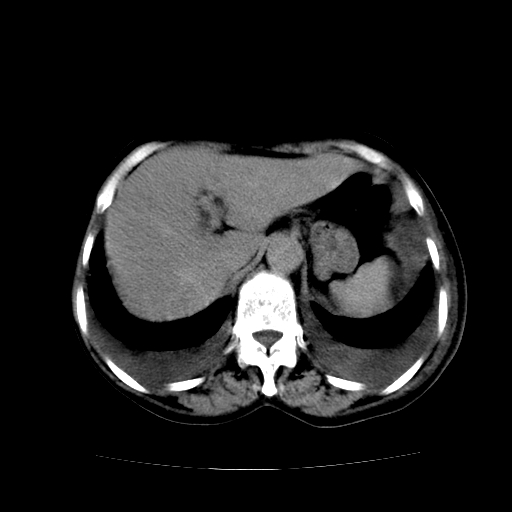

癌性淋巴管炎,肝脏转移,瓷胆囊

1)左侧乳腺癌并左侧腋窝及纵隔淋巴结转移,两肺淋巴道转移(癌性淋巴管炎),肝脏多发性转移。2)双侧胸腔积液。3)慢性胆囊炎。

5、肝转移瘤;

6、瓷胆囊。

1)左侧乳腺癌并左侧腋窝及纵隔淋巴结转移,肝脏多发性转移。2)双侧胸腔积液伴双肺蝶翼样磨玻璃高密度影,双侧肺门血管影增粗(图像不全,肺门层面没纵隔窗),考虑心功能不全所致。3)慢性胆囊炎伴壁钙化。

左侧乳腺癌并左侧腋窝及纵隔淋巴结转移,两肺淋巴道转移(癌性淋巴管炎),肝脏多发性转移。2)双侧胸腔积液。3)瓷胆囊